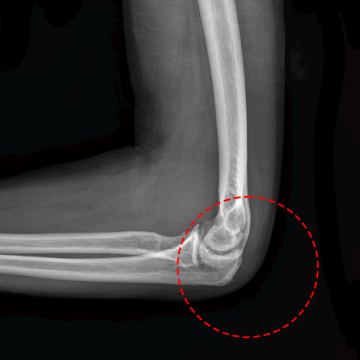

[수술전 X-ray]

21년 9월 10일